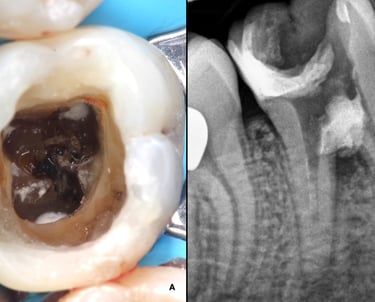

Es el procedimiento para limpiar, desinfectar y sellar los conductos internos del diente cuando la pulpa está infectada o inflamada. Es esencial para salvar el diente.

Tratamiento de Conducto

Se trata de una infección en el extremo de la raíz del diente que forma una acumulación de pus. El tratamiento incluye la limpieza y desinfección del conducto radicular y, en algunos casos, el drenaje del absceso.

Tratamiento de Absceso Periapical